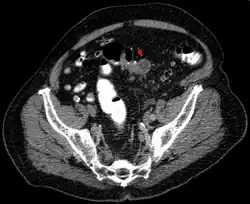

An Symptomen besteht ein plötzlich auftretender Schmerz über dem betroffenen Darmabschnitt am häufigsten im linken Unterbauch (deshalb auch Linksseiten-Appendizitis) oft mit Ausstrahlung in den Rücken und mit einer auf diesen Bereich begrenzten Peritonitis. Daneben sind häufige Symptome Fieber, Übelkeit, Erbrechen, eine Veränderung des Stuhlverhaltens von Durchfall bis Verstopfung mit Eiter und Schleim im Stuhl und Schwierigkeiten beim Wasserlassen, Dysurie genannt. In den Laborwerten fallen eine Erhöhung des CRPs und der Leukozyten auf. Teilweise kann bei der Untersuchung des Bauches des Betroffenen ein walzenförmiger Tumor (Tumor im Sinne einer raumfordernden Geschwulst) getastet werden. Die weitere Diagnostik erfolgt u. a. mit dem Ultraschall und einer CT-Untersuchung des Bauches. Bei der akuten Divertikulitis wird die Durchführung einer Darmspiegelung wegen des Risikos einer Perforation vermieden. Darmspiegelungen werden lediglich in Intervallen durchgeführt, um andere – insbesondere bösartige – Erkrankungen auszuschließen.[8]